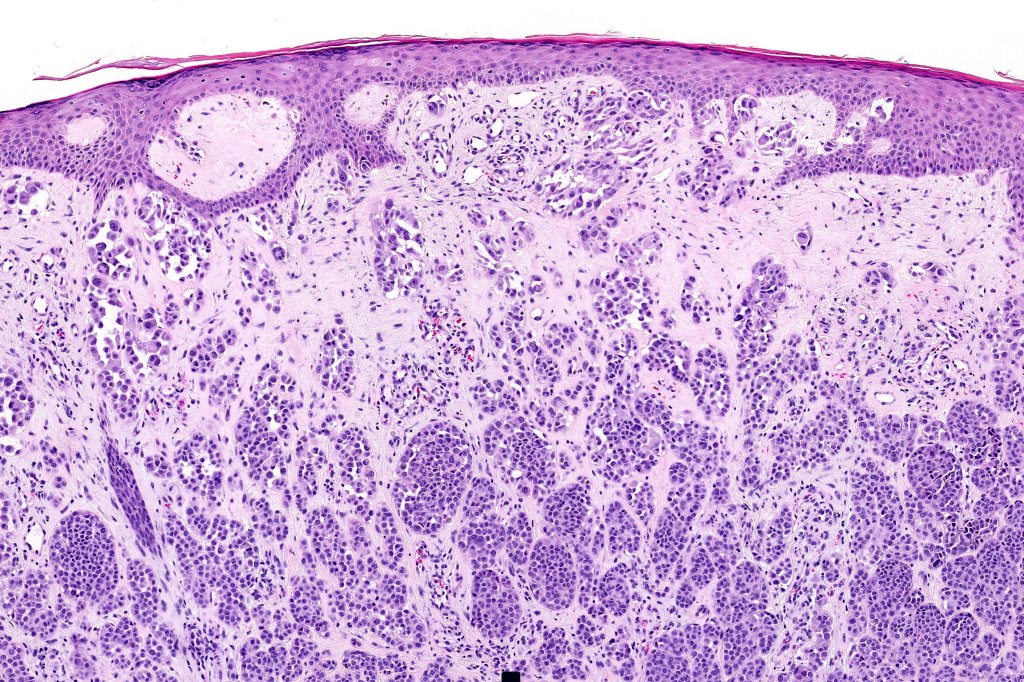

•May show effacement/consumption of epidermis or ulceration

•Peripheral Pagetoid spread

•Large nodules which often show impaired maturation